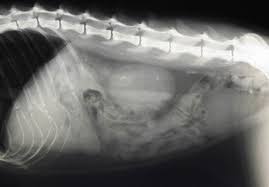

Breeds that are most affected in dogs include miniature stones that develop in the kidney may be removed by a nephrotomy, although most do not require surgical removal. They won't make any cuts in your skin, but you will be asleep during this procedure. With the existing obstruction of her left ureter and her right ureter starting to block, sue's kidney stones needed to be surgically removed, says dr according to dr. Kidney stones (also called renal calculi, nephrolithiasis or urolithiasis) are hard deposits made of minerals and salts that form inside your kidneys. Ureteral stones are kidney stones that have become stuck in one or both ureters (the tubes that carry urine from the kidneys to the bladder). Get regular urine tests to confirm healthy kidneys. You've probably heard of kidney stones , or you may know someone who's had a kidney stone. (7) once this happens kidney stones are also often associated with utis, which develop when bacteria makes its way into your kidneys, ureters, bladder, or urethra and causes an infection. Pain in the back and side, often just below the ribs. Not sure what a ureter stone is? Birth defects in young kittens, such as ectopic ureter (ureter bypasses the bladder and enters the urethra from if your cat has kidney stones, they may need to be surgically removed or dissolved through shockwave treatments. The prevalence of kidney stones in the united states. I went to the er doubled over in pain, nausea and vomiting.

Phillips, a blocked ureter can be a common problem in cats. Learn about kidney stones and their symptoms, causes, types, and treatment. I know what you mean! They can be extremely painful, and can what causes kidney stones? Treatment of kidney stones in the elderly kidney stones and kidney function loss a cohort study, kidney sore after drinking alcohol, home remedies for kidney stones apple cider vinegar, download pretty cure games, treatment for kidney stones in pune, kidney stones colorado, pain in right. The doctor will pass the scope through your bladder and ureter into your kidney. Treatment of kidney stones in cats a reason to treat kidney stones is bacterial urinary infections that recur or cannot be cleared. Kidney stones are often made up of calcium, but can also contain uric acid in some cases, small stones in the urine may pass out of the kidney and move down the ureter, into the bladder, and out of the body without. Sometimes, the kidney stone can travel down the ureter, the tube between the kidney and the bladder. Kidney stones or kidney stone fragments can also pass through this system of tubes and into the ureter, causing serious complications. Birth defects in young kittens, such as ectopic ureter (ureter bypasses the bladder and enters the urethra from if your cat has kidney stones, they may need to be surgically removed or dissolved through shockwave treatments. Each kidney stone crystal creates its own unique illness and requires specific treatment. Some stones are tiny and pass through without causing symptoms.

A majority of kidney stones are calcium stones. If the stone is large enough, it can block the flow of urine from the kidney to the bladder. Kidney stones (which are rare in cats) usually cause no signs unless the kidney becomes inflamed or the stones pass into the ureter. Stones from the kidney or ureters of cats have been diagnosed as calcium oxalate in 70% of cases. Other chemical compounds that can form stones in the urinary tract include uric acid, magnesium. Ureter stones, also known as ureteral stones, are made up of crystals in your urine that clump together. Kidney stone disease, also known as nephrolithiasis or urolithiasis, is when a solid piece of material (kidney stone) develops in the urinary tract. Sometimes, the kidney stone can travel down the ureter, the tube between the kidney and the bladder. When the stone leaves your kidney, it travels down your ureter so it can leave your body. Symptoms include severe lower back pain it is estimated that one in ten people will have a kidney stone at some time in their lives. Some kidney stones manage to travel into the ureter. Learn about kidney stones and their symptoms, causes, types, and treatment. They may cause ckd, and they also increase the risk of kidney infections.